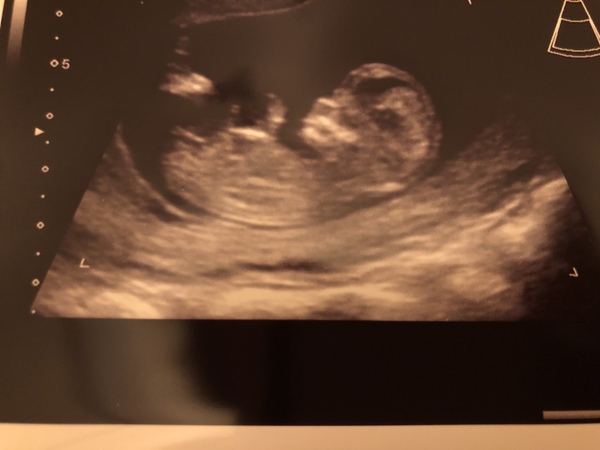

Hi everyone, I had my scan today. Been trying to guess the sex all afternoon but I don’t get this nub and skull theory haha!

Congratulations @hjbows88 that's a lovely photo, looks girly to me 🎀( no expect just been obsessing over the nub theory lol ) xx

Thanks for the guess @AmyMaria2 - I thought girl too but don’t trust my ability to apply the nub or skull theory 😂😂 hope everyone is doing ok today x

Amazing scan today! Baby was having a little disco dance in there so took ages to get a good pic, saw him/her waving, hiccuping, all just incredible! Suddenly feels very real!! 😍😍 Still have to wait a week for the screening test results but I'm hopeful!! 🤞🤞